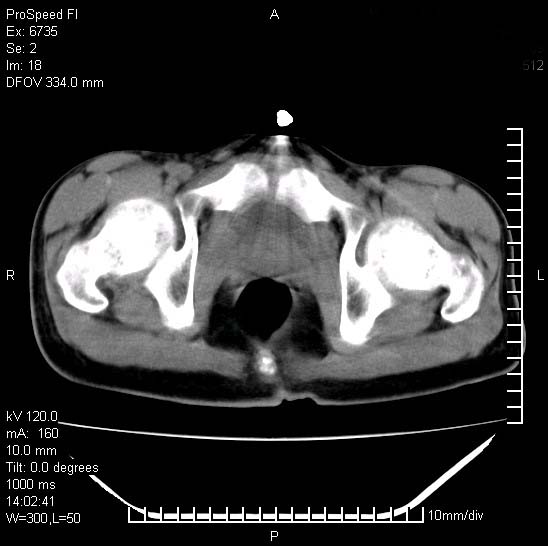

患者自诉胯部疼痛两年余,在当地服用中药,半月前至本院考虑骶髂关节结核,给予抗痨治疗。现发展至右下肢疼痛明显,活动受限,以膝关节处明显,拍膝关节平片无明显异常。

两侧骶骼关节改变,考虑强直性脊炎

左侧骶髂关节面限局性骨破坏,边缘硬化关节腔见钙化物;不出外tb

右侧骶髂关节也有类似改变,只是较左侧轻,首先考虑强直性脊柱炎,不除外结核,建议作hla-b27检查。

典型强脊炎改变,髋关节亦有累及

符合强直性脊柱炎表现。